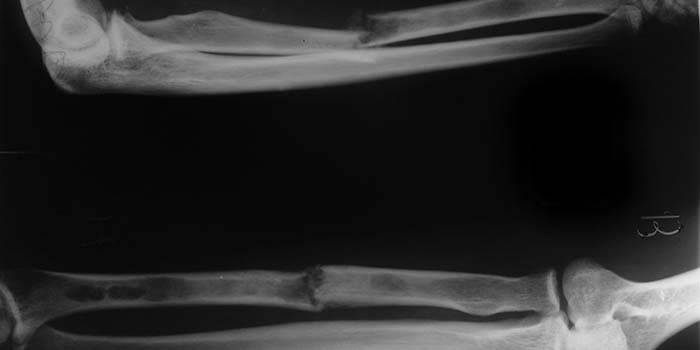

Fratura de raio

Qualquer lesão no antebraço não representa um sério perigo para a vida do paciente, mas pode causar conseqüências desagradáveis devido a perturbações no funcionamento dos sistemas nervoso e vascular. As fraturas do rádio são dolorosas, muitas vezes após elas a funcionalidade dos membros superiores é prejudicada. Com diagnóstico adequado e tratamento cuidadoso, o paciente é totalmente restaurado em um quarto de ano. As fraturas patológicas e traumáticas são diferenciadas dependendo do método de dano, e fechadas ou abertas são determinadas pelo grau de dano à pele.

Em um lugar típico

Muitas vezes o osso é propenso a fraturas no lugar mais fino, porque essas lesões são referidas como uma fratura do rádio em um local típico. Este tipo de dano no antebraço é muito comum, representando 15% de todas as lesões no esqueleto humano. Fraturas típicas ocorrem a aproximadamente 3 cm do punho e são chamadas de metaepífise distal. Segundo as estatísticas, mais frequentemente quebram a mão esquerda do que a direita. Fraturas típicas do feixe na prática internacional código atribuído CID S52.5.

A situação na qual os fragmentos da epimetáfise, deixando o lugar habitual, são deslocados para o lado - esta é uma mudança. Uma mão com tal dano dói muito, inchaços aumentam, até mesmo por sinais externos pode ser visto que os ossos não são colocados corretamente. Uma fratura do raio do braço com um turno envolve o reposicionamento e a colocação de um berço, em casos difíceis - uma operação. Para o crescimento adequado, é necessário aplicar o gesso por até um mês. Informações sobre como remover o edema após uma fratura do osso radial são melhor obtidas de um médico, a automedicação pode prejudicar a si mesmo.